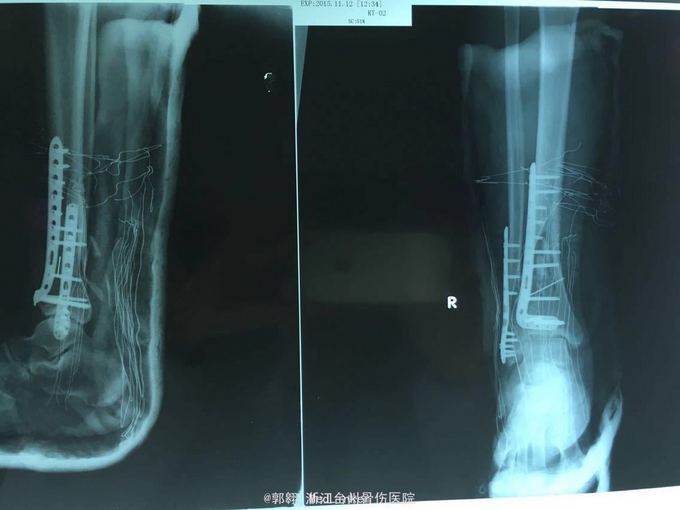

车祸致右小腿出血畸形疼痛一小时 患者因车祸受伤右小腿出血畸形疼痛到医院就治,当时诊断为右小腿胫腓骨下段开放粉碎性骨折。急诊在麻醉下行清创骨折复位内固定术,术后发现小腿皮肤损伤坏死,给予VSD吸附治疗,现因小腿皮肤软组织坏死,肌腱、骨折、钢板外露转科治疗。

诊断:右小腿胫腓骨下段开放骨折术后皮肤软组织坏死伴组织缺损 处理:在麻醉下行清创 去除坏死组织、取股前外侧皮瓣游离移植修复创面、阔筋膜移植修补胫前肌腱和伸拇肌腱,血管吻合胫前动脉并桥接足背动脉,供区部分创面不能直接缝合植皮关闭。